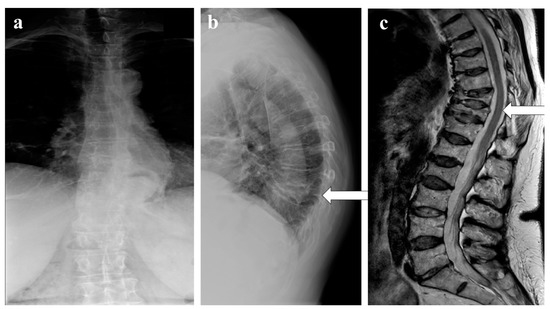

12. Chronic Recurrent Multifocal Osteomyelitis